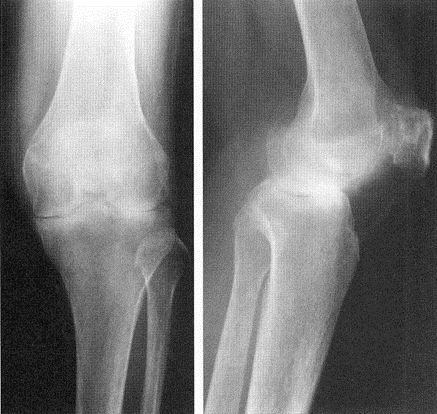

②関節リウマチ(下図)

③半月板損傷(下図)

④歩行中左ひざが痛くなった→骨粗鬆症による脆弱性骨折(下図)